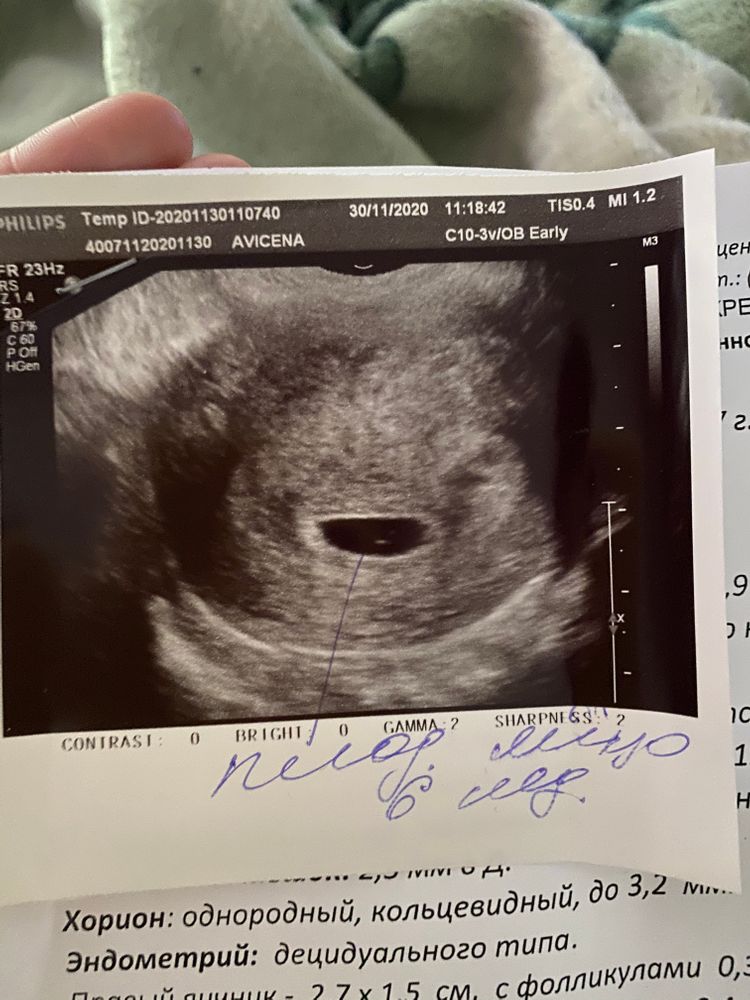

Как я ждала этого дня, переживала чтобы все было отлично. Начиталась про вм и неделю не спала толком. Девчонки, посмотрите все хорошо же ? По срокам завтра 6 недель